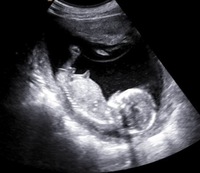

赤ちゃんの性別判定 現在妊娠8ヶ月の妊婦です! 私の通ってる病院は初期から聞いてもないのに積極的に性別を教えてくれる病院で(^^;) 17週頃にちょうど赤ちゃんの小股部分がチラっと映った時に、突起物!?のようなものが出てるから男の子かも! 縦と横方向からだけではなく、色々な方向から赤ちゃんが見えるようになるため、早い人ではこの頃に性別を産婦人科の先生から知らされます。 しかし女の子は以下に引用するように、5ヶ月ではまだわからないことが多いです。 女の子は男の子特有のシンボルが足の間にはなく、外陰部らへんに女性の大陰唇と分かる割れ目が見えると女の子です。 こちらはよ~く見てみないと分か

医師が性別を判断する決めては、男女それぞれの外性器です。 XXの染色体をもつ女の子の未分化性線は子宮や膣、XYの染色体をもつ男の子の未分化性線は精巣や陰嚢、陰茎を作ります。 しかし、妊娠初期の段階では胎児が小さすぎるため、エコー検査では判別ができません。 妊娠7~8週目くらいで性の分化が始まって男女の性器が作られ始め、 11~12週目になって、男の子には男性Q赤ちゃんの性別 現在妊娠5ヶ月です。 赤ちゃんの性別が早ければ次の健診でわかるかなーとどきどきしていますが、皆さんはいつ頃わかりましたか? 一度言われた性別が訂正されることもあるようなので確定ではないと思いますが、わかった時期や性別 うちの義母は女の子希望です。 息子の時に男の子だったと言ったら 手で顔を覆い 赤ちゃんの性別が判明した時期は、6~7ヶ月頃が約半数 6~7ヶ月頃が最も多く、約半数(51%)でした。4~5ヶ月頃が28%、8~9ヶ月頃が14%となりました。